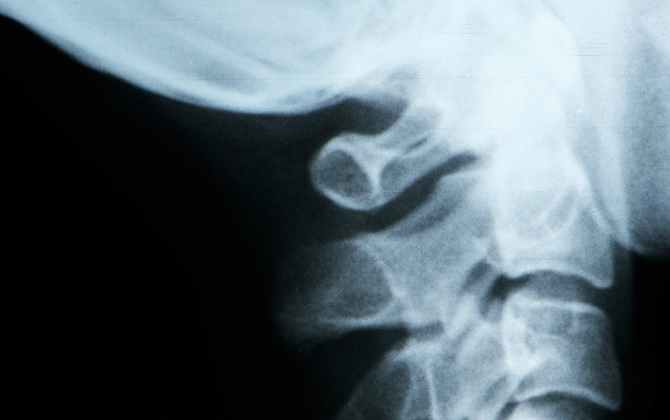

Incidence, circumstances, treatment and outcome of high-level cervical spinal fracture without associated spinal cord injury in New South Wales, Australia over a 12 year period.